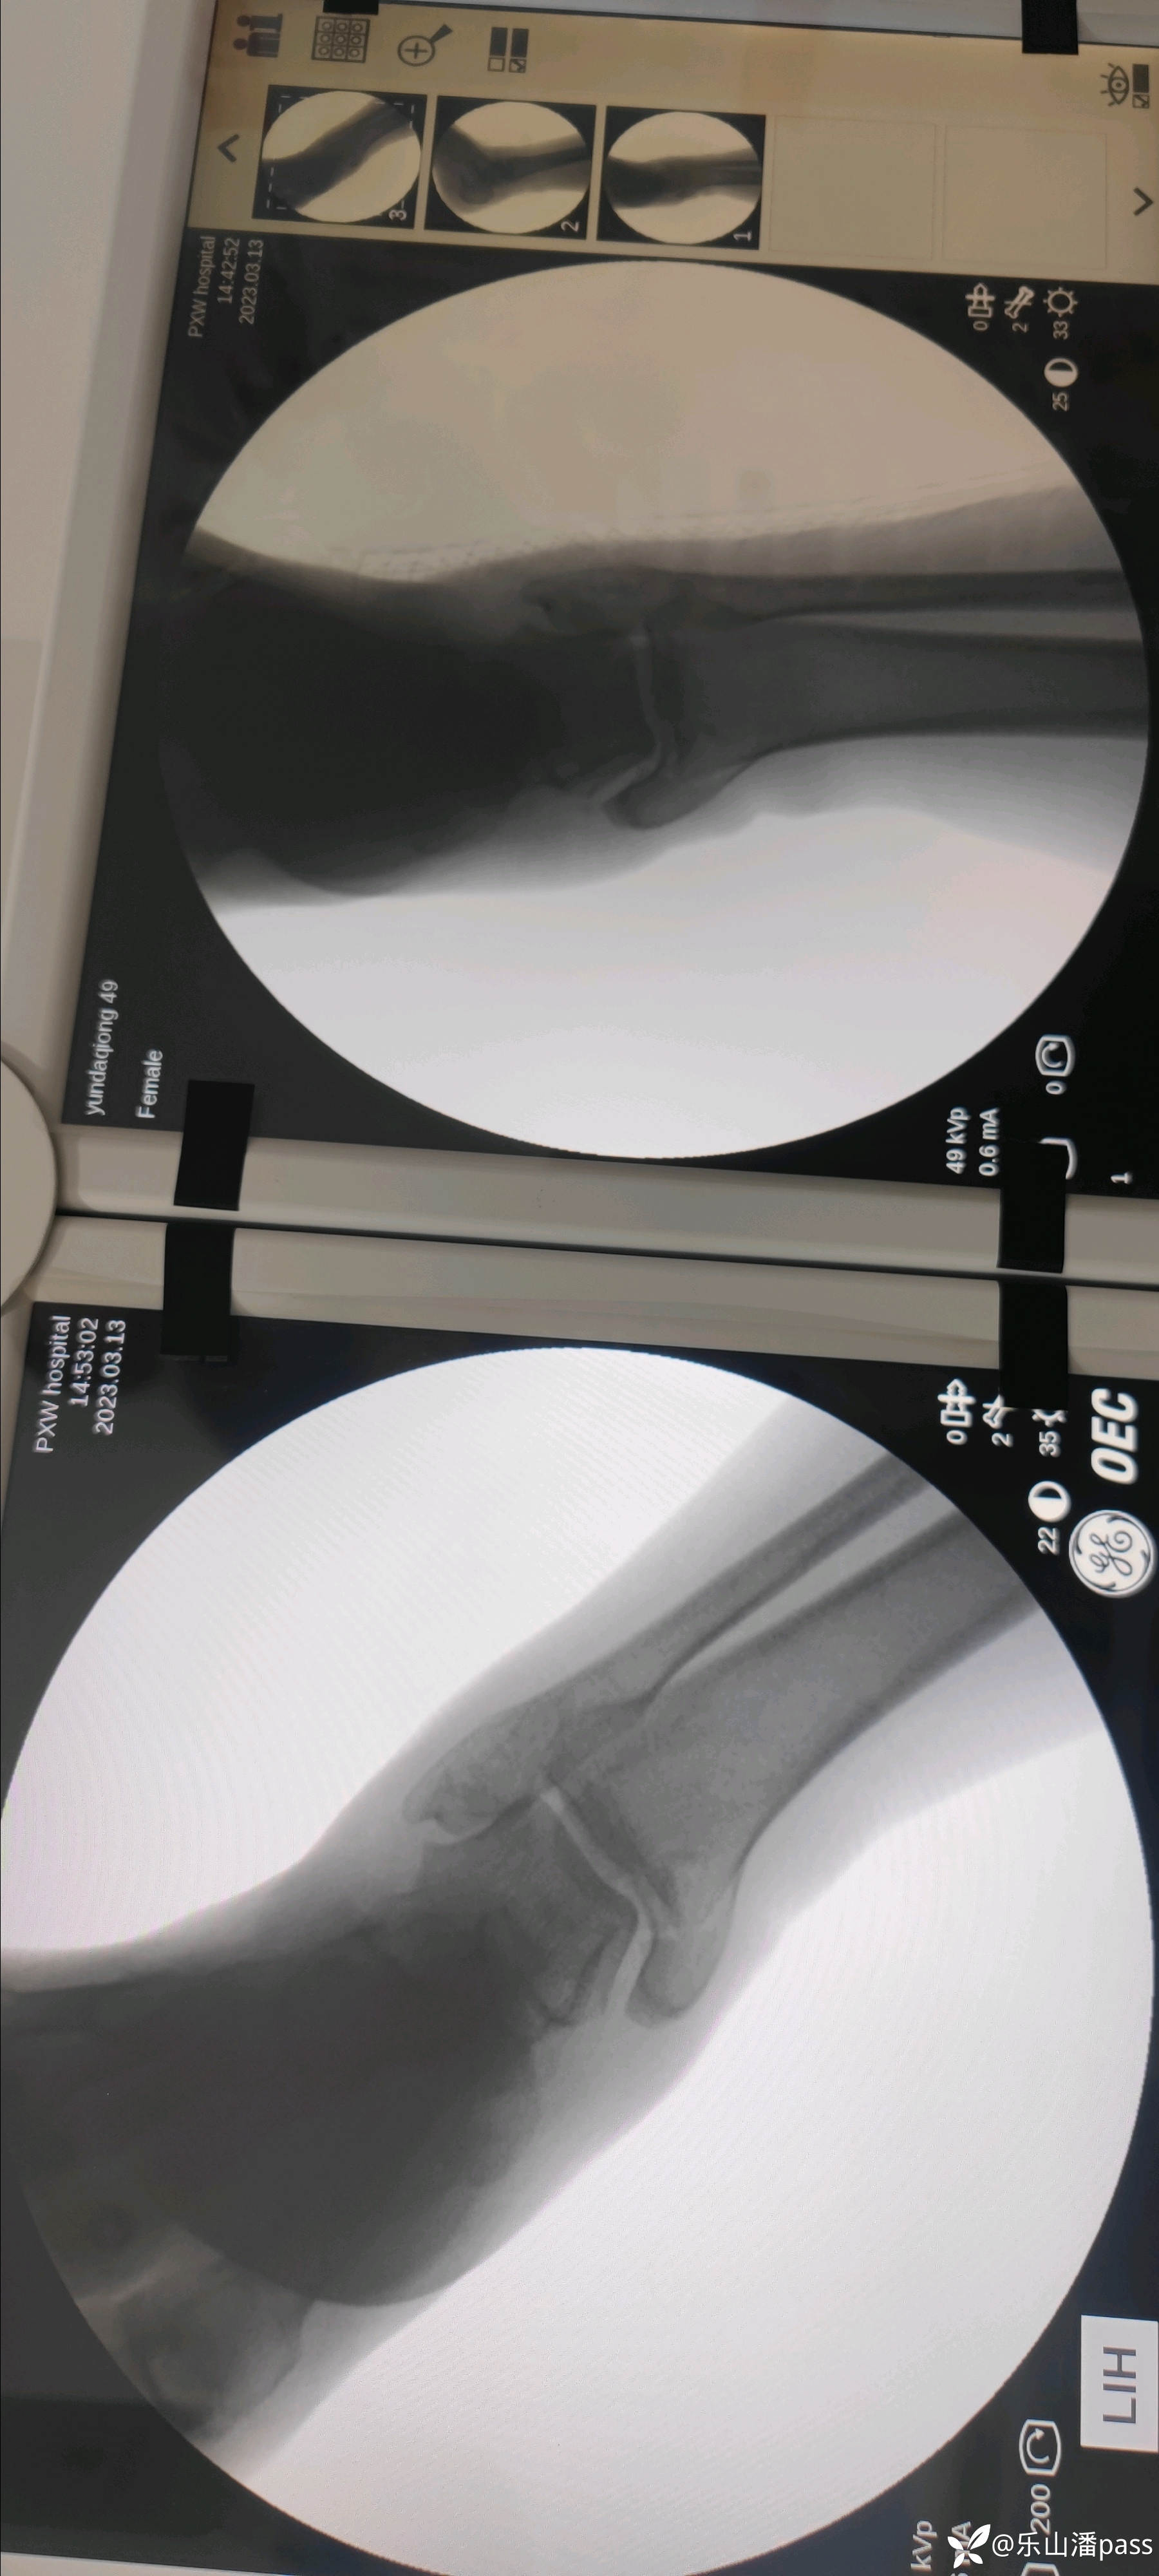

患者女性,自述十个月前外伤,患者就在当地医疗机构处理(具体处置不详)。原始片如下:

img